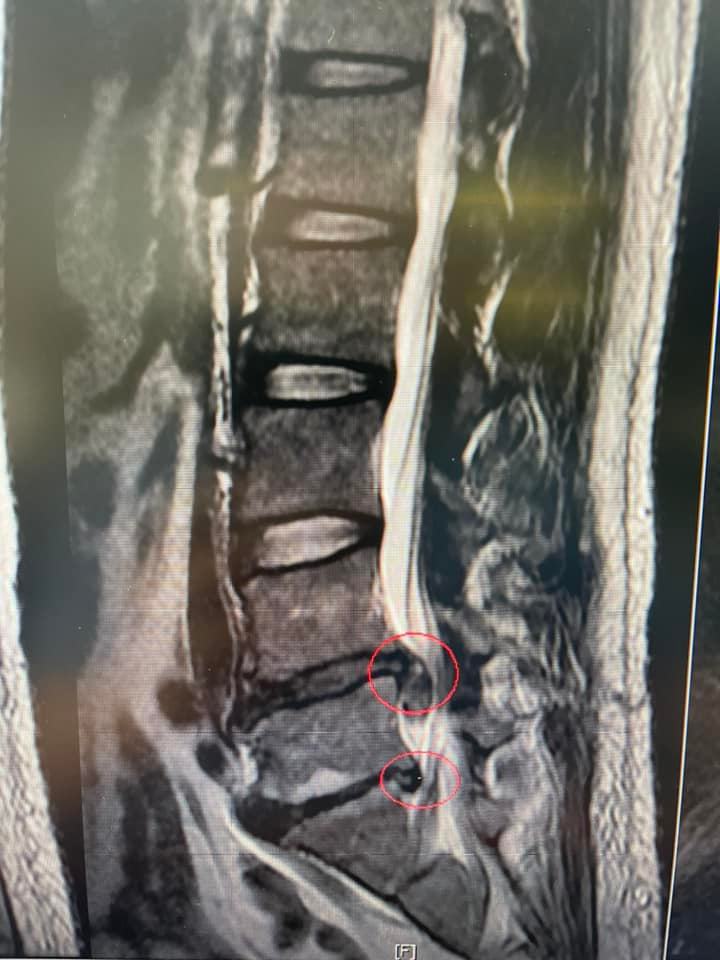

為了救他(椎間盤巨大突出患者),來診前已經無法趴跟躺,只能用很怪異角度斜躺在治療床上,哥卯勁全力軟Q神龍擺尾也要針下去!! PS.脊椎微創針刀醫師的日常生活❤️

為了救他(椎間盤巨大突出患者),來診前已經無法趴跟躺,只能用很怪異角度斜躺在治療床上,哥卯勁全力軟Q神龍擺尾也要針下去!!